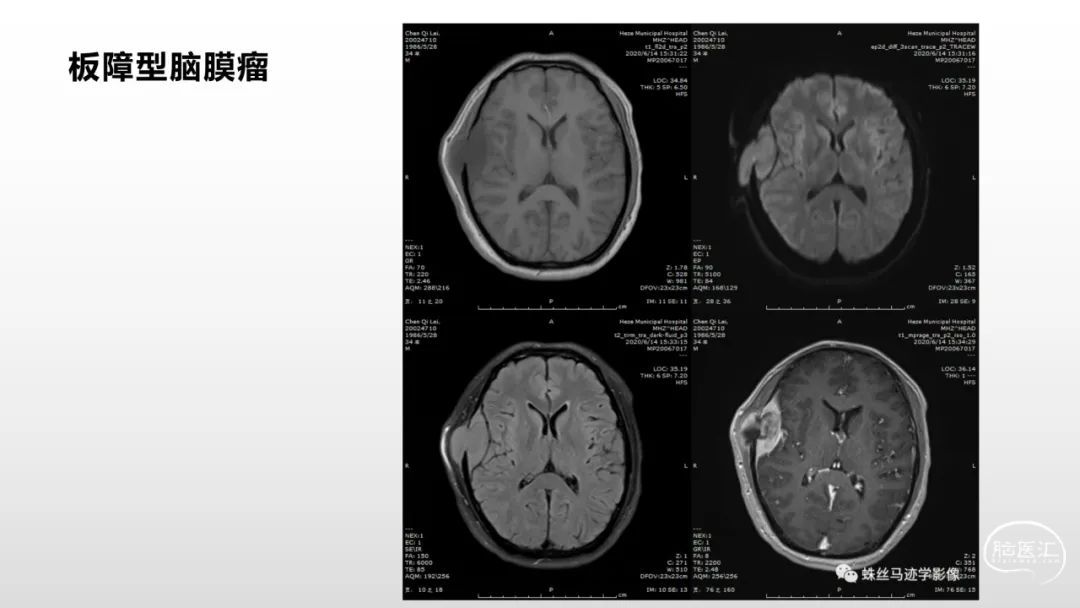

颅脑影像诊断基础知识讲座:脑膜病变